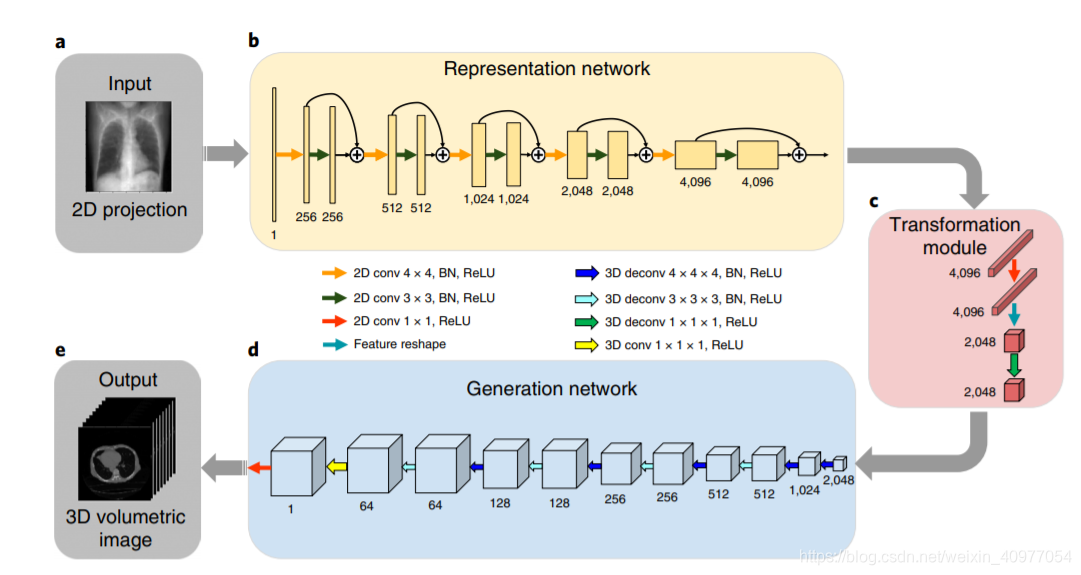

主要对Liyue Shen等人提出的通过单个DRR图像生成三维CT数据的方法进行了复现。

2.2.1 网络结构

表征层网络

一个二维的残差网络,主要用于提取DRR图像中的特征信息

转化模块

经过表征层网络寻来你后得到4096×4×4的tensor,通过transform模块将这个tensor转为2048×2×4×4

生成网络

类似一个解码器,根据二维图像提取的特征生成三维的CT数据

2.2.2 超参数设置

激活函数选用ReLU

代价函数选用均方误差(MSE)

优化器论文中用了Adam

实际用的时候使用Adam在反向传播的时候计算量很大,网络跑不动,所以使用了SGD,且momentum=0才跑得动

optimizer = torch.optim.SGD(model.parameters(), lr=0.001, momentum=0)

epoch size = 100 , min-bath size = 1